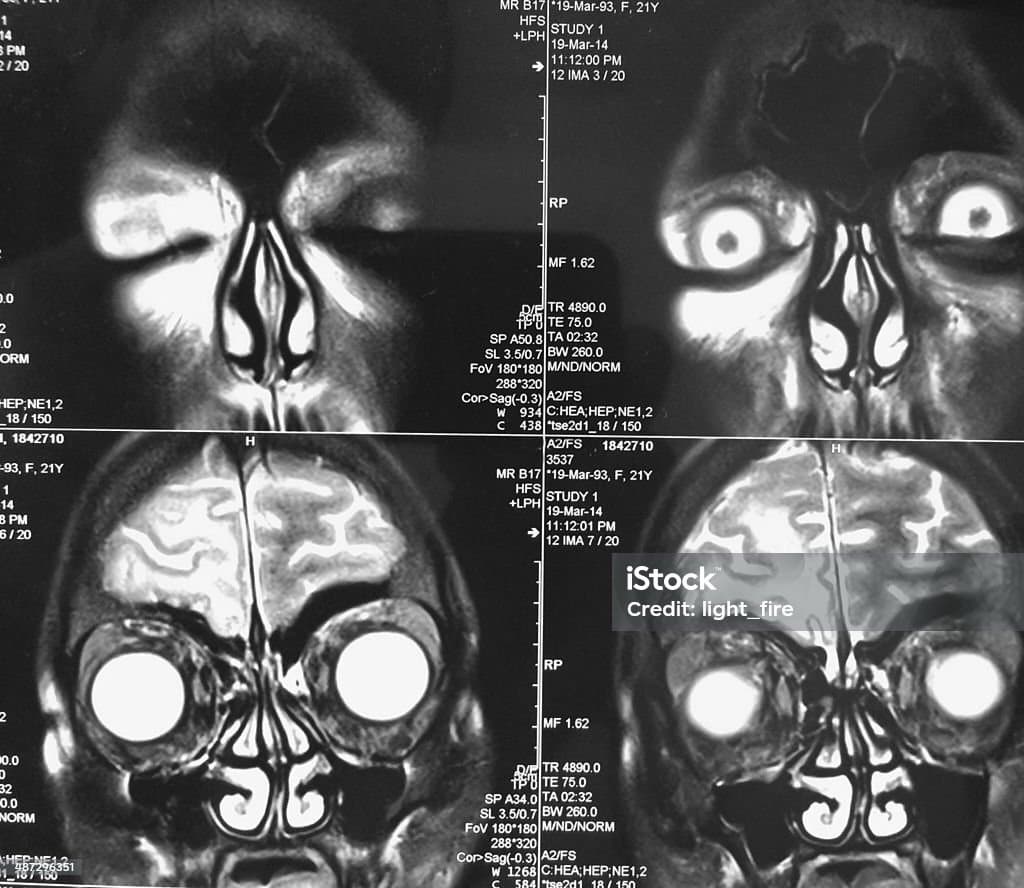

비중격만곡증(鼻中隔彎曲症, Deviated Nasal Septum)은 코 내부의 비중격(콧속을 좌우로 나누는 연골과 뼈로 이루어진 구조물)이 한쪽으로 휘어져 있는 상태를 말합니다. 일반적으로 경미한 비중격만곡은 많은 사람에게서 발견되지만, 심할 경우 코막힘, 호흡 곤란, 만성 부비동염(축농증), 코골이 및 수면 무호흡증 등의 증상을 유발할 수 있습니다.